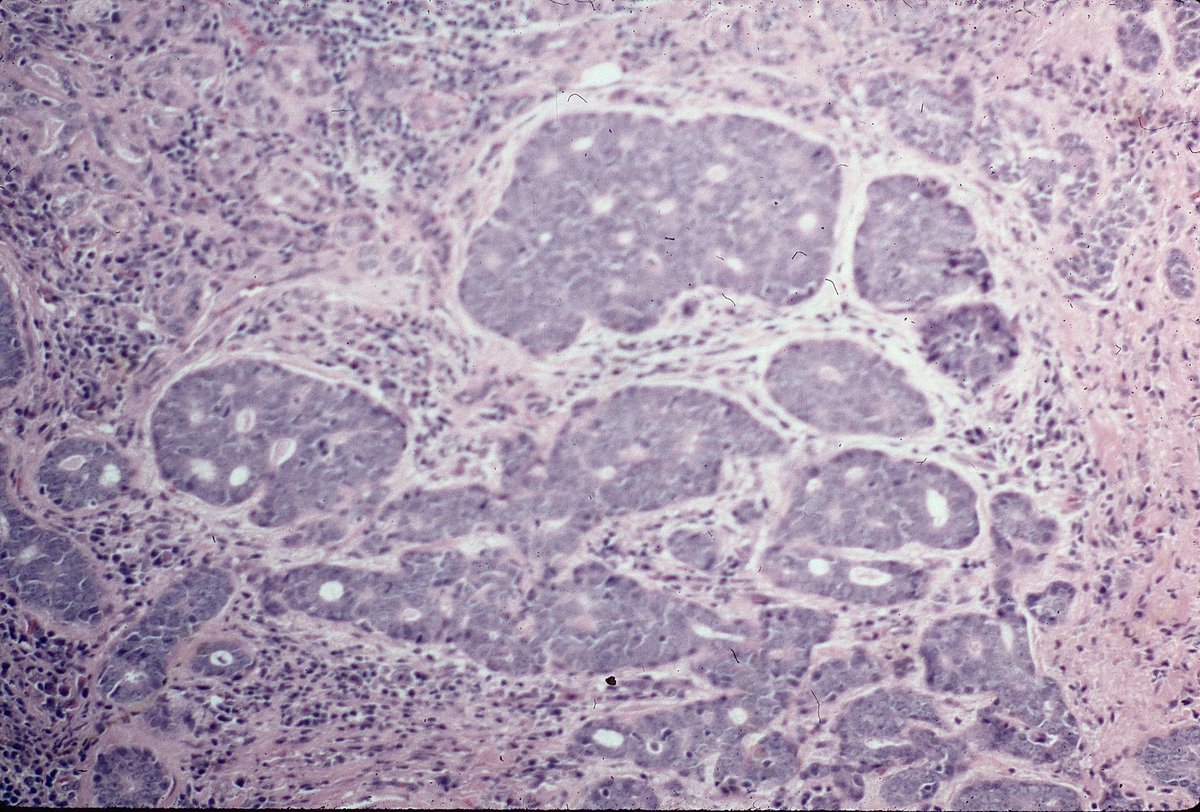

what do u think of this case plz..20 y M huge well circumscribes lung mass. necrosis present. focal SMA&WT1. Neg CK,S100,HMB45,DESMIN,CD34

#LUNGPATH#BSTPATH@yro854@DrRolaAli@DrGeeONE@JScapaPathMD@histiocytosisX@01sth02@MAHoureih@pathnoob@MELanocyteMD@AMubeen_Pathpic.twitter.com/ti56gmtnvk